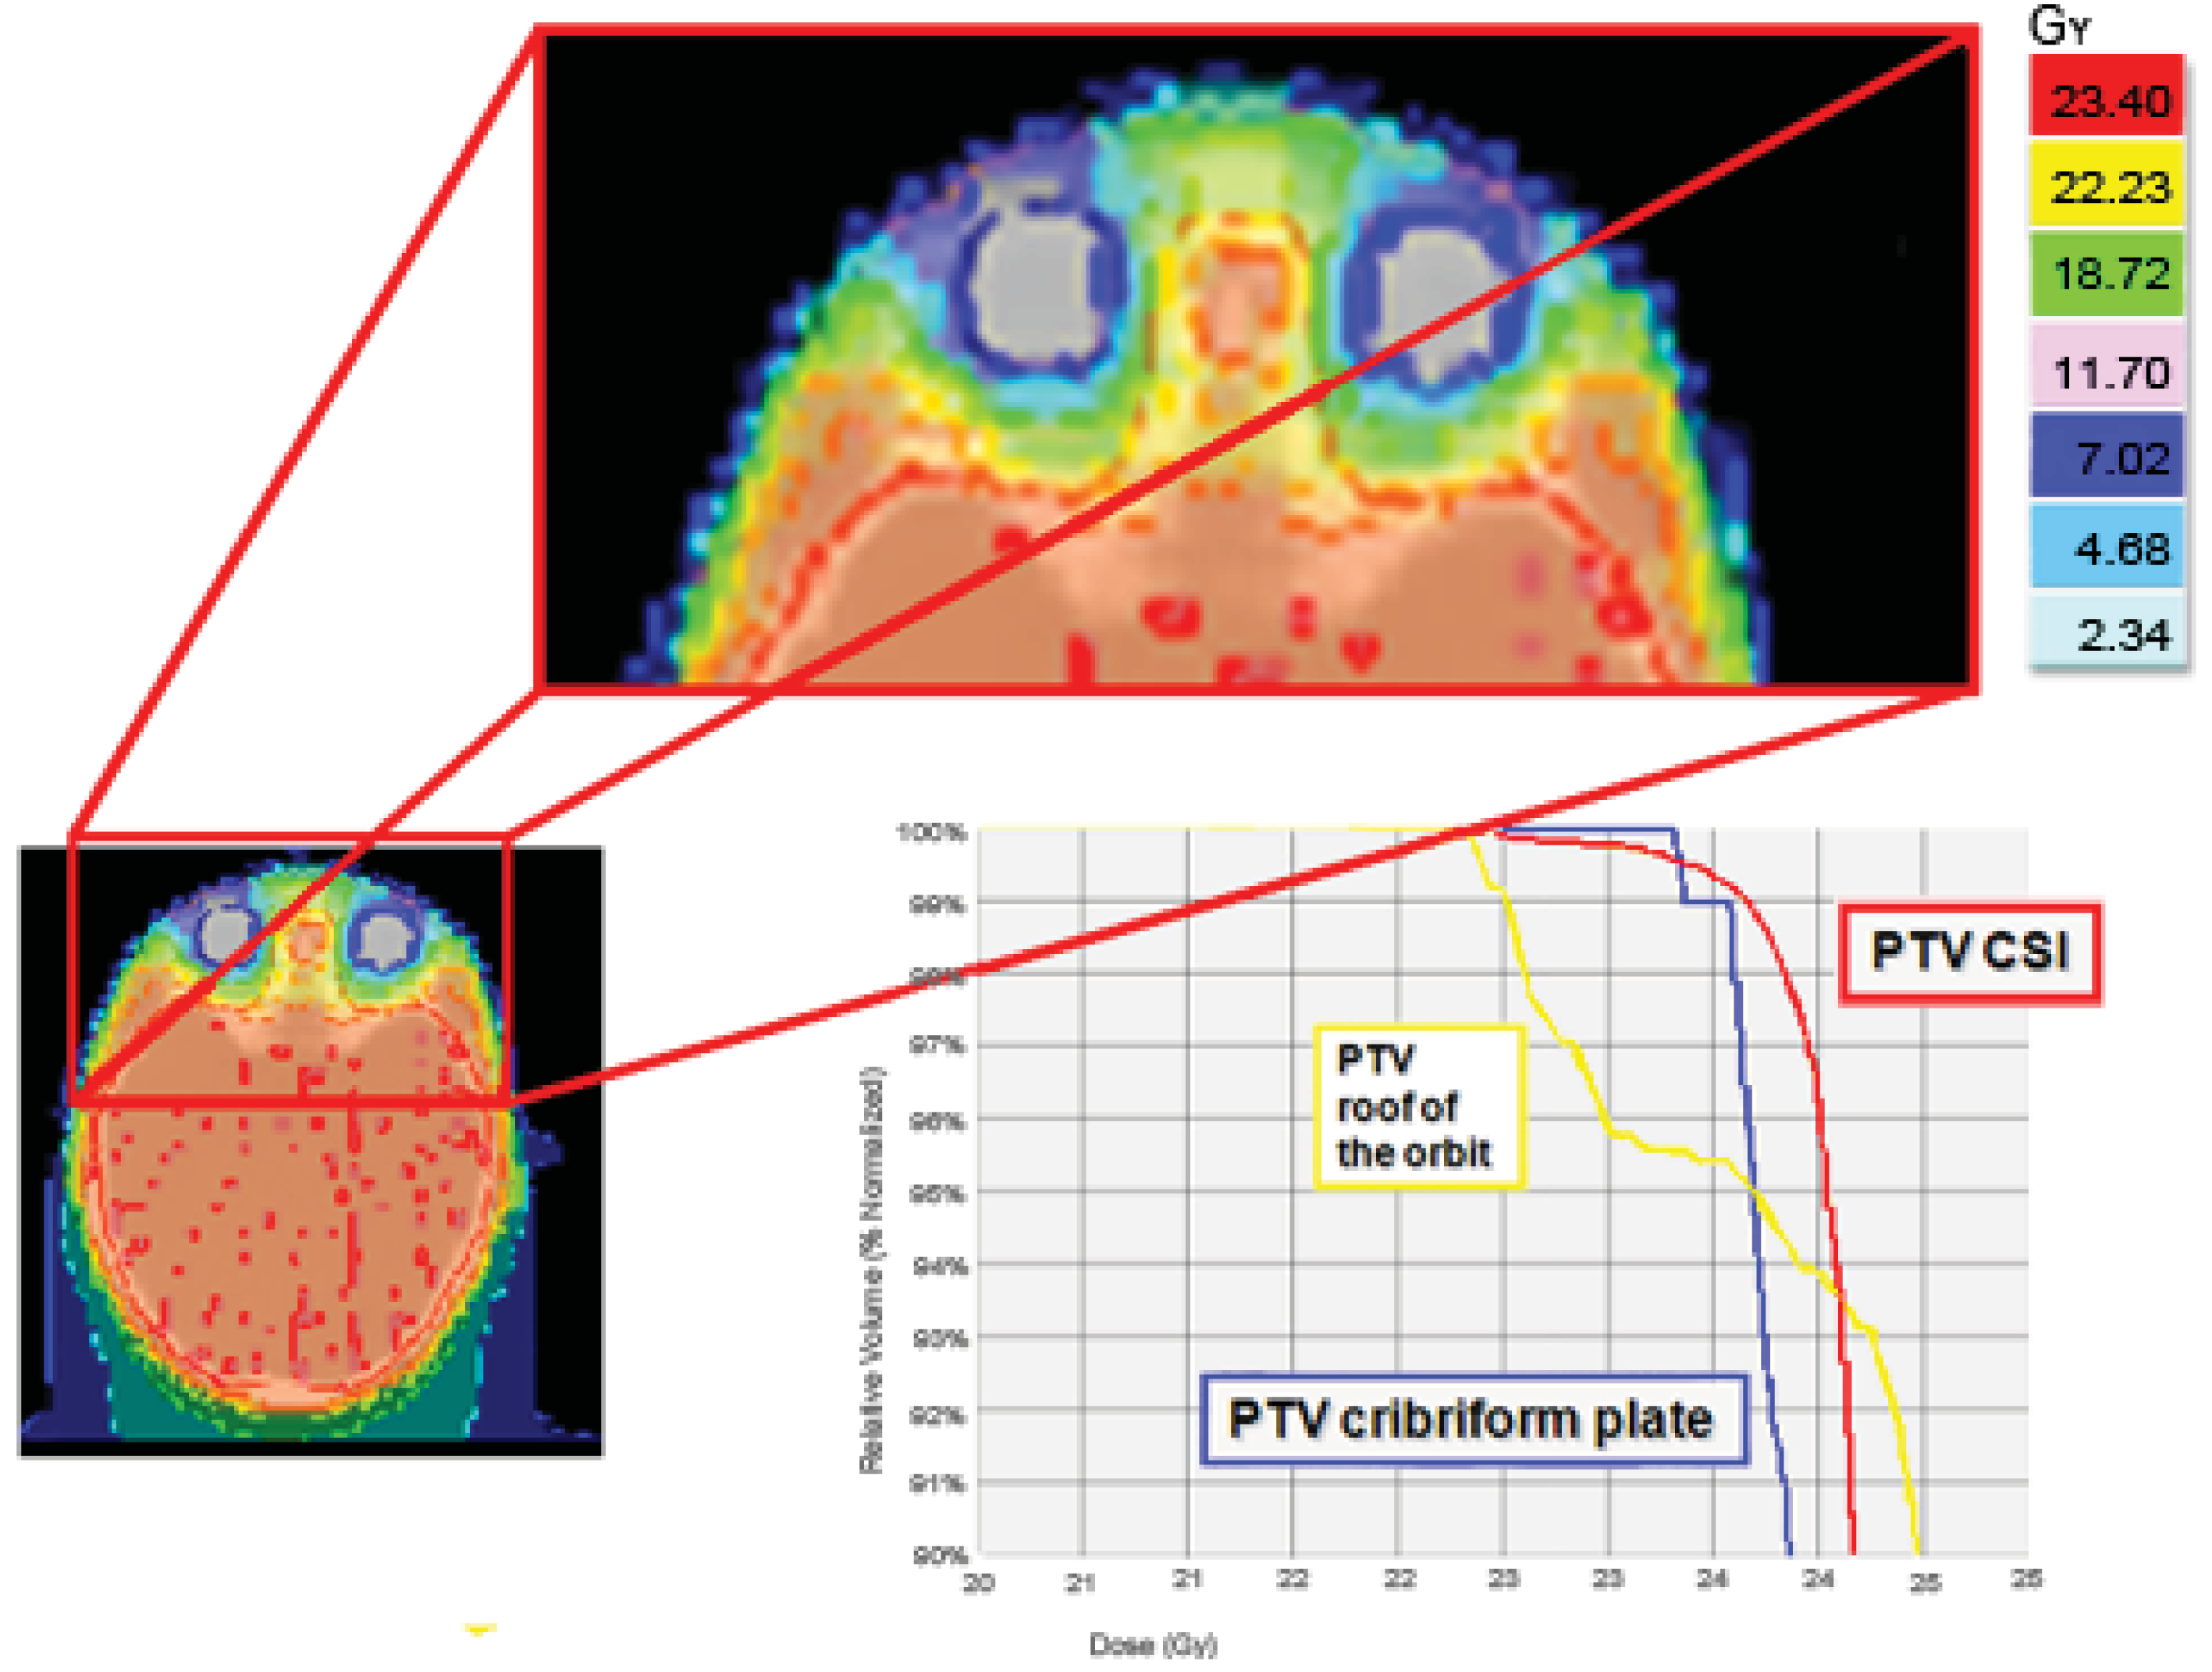

The cribriform plate is a possible site of meningeal relapse. Adequate coverage of this structure means that superior orbital tissue is included in the treatment field. An inspection of a central axis slice through the eye level shows a good ocular sparing with HT, with a 25 mm fan beam and by building a “tuning eye structure” in the anterior-bulbar space. However, the cribriform plate is not covered as well as the rest of the craniospinal PTV. For this reason we usually build some extra PTV to better control these critical areas. A good result both in the ocular area and the cribriform plate PTV was also obtained with a 10 mm fan beam, but with a total treatment time of about 40 minutes; unacceptable for a child treated daily with sedation (Figure 4).